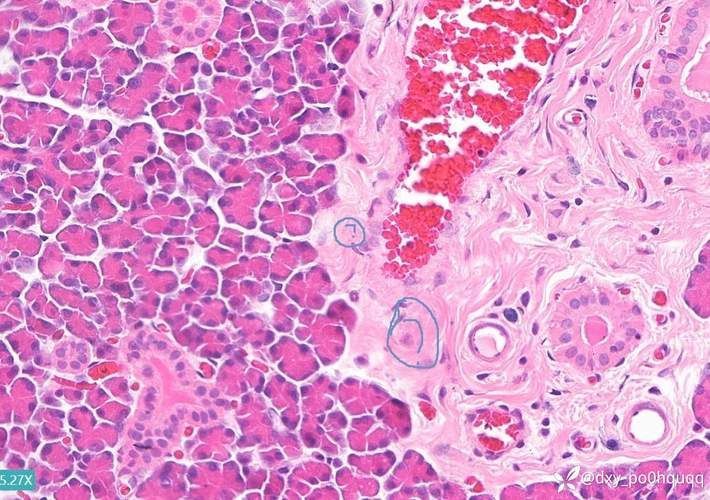

顯微鏡下特征(關鍵鑒別點):

- 指環蟲:蟲體呈蠕蟲狀,長約0.5–2mm,具兩個錨狀附著器,可見顎片;

- 鰓隱鞭蟲:柳葉形,前端具兩根不等長鞭毛,后鞭毛與波動膜相連,運動迅捷;

- 小瓜蟲:鰓絲上可見白色點狀胞囊(直徑0.2–0.5mm),蟲體成熟后破裂釋放幼蟲。

三、確診金標準:鰓絲鏡檢操作流程

鏡檢是唯一確診手段,無需昂貴設備,家庭養殖者可自行完成:

- 捕撈病魚:用網輕撈,避免擠壓鰓部;

- 刮取樣本:用潔凈牙簽或玻璃片輕刮一側鰓絲,刮取黏液與組織碎屑;

- 制片觀察:將刮取物置于載玻片,加1滴清水,蓋上蓋玻片;

- 顯微鏡檢查:使用40–400倍光學顯微鏡,先低倍(10×)定位,再高倍(40×)觀察蟲體形態。

注意:鏡檢應在10分鐘內完成,避免蟲體脫水變形。若無顯微鏡,可送至專業水族醫院或水產站檢測。